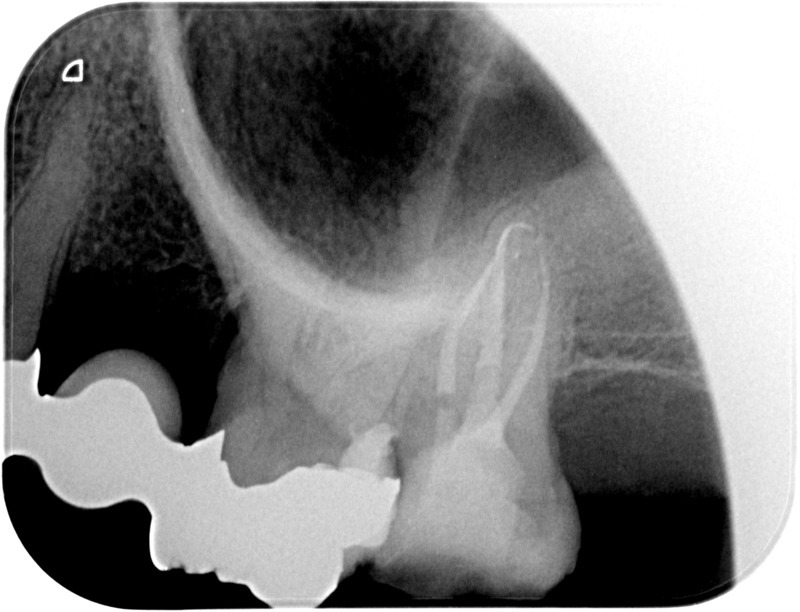

• Apexification : Chez le jeune enfant, une dent immature victime d’un traumatisme ou d’une carie volumineuse peut poser problème. Si la pulpe agressée se nécrose, alors la racine ne s’édifie plus et une lésion inflammatoire se développe au niveau osseux. L’apexification, par apposition d’un matériau biocompatible dans la racine, cherche à induire la formation d’une barrière artificielle à l’extrémité de celle-ci, et permettre la cicatrisation de la lésion dans le but de maintenir la dent en bouche à long terme.

Avant